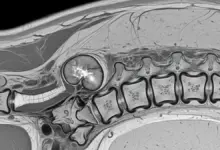

- Raio-x, tomografia ou ressonância da coluna com descrição de fraturas por compressão;